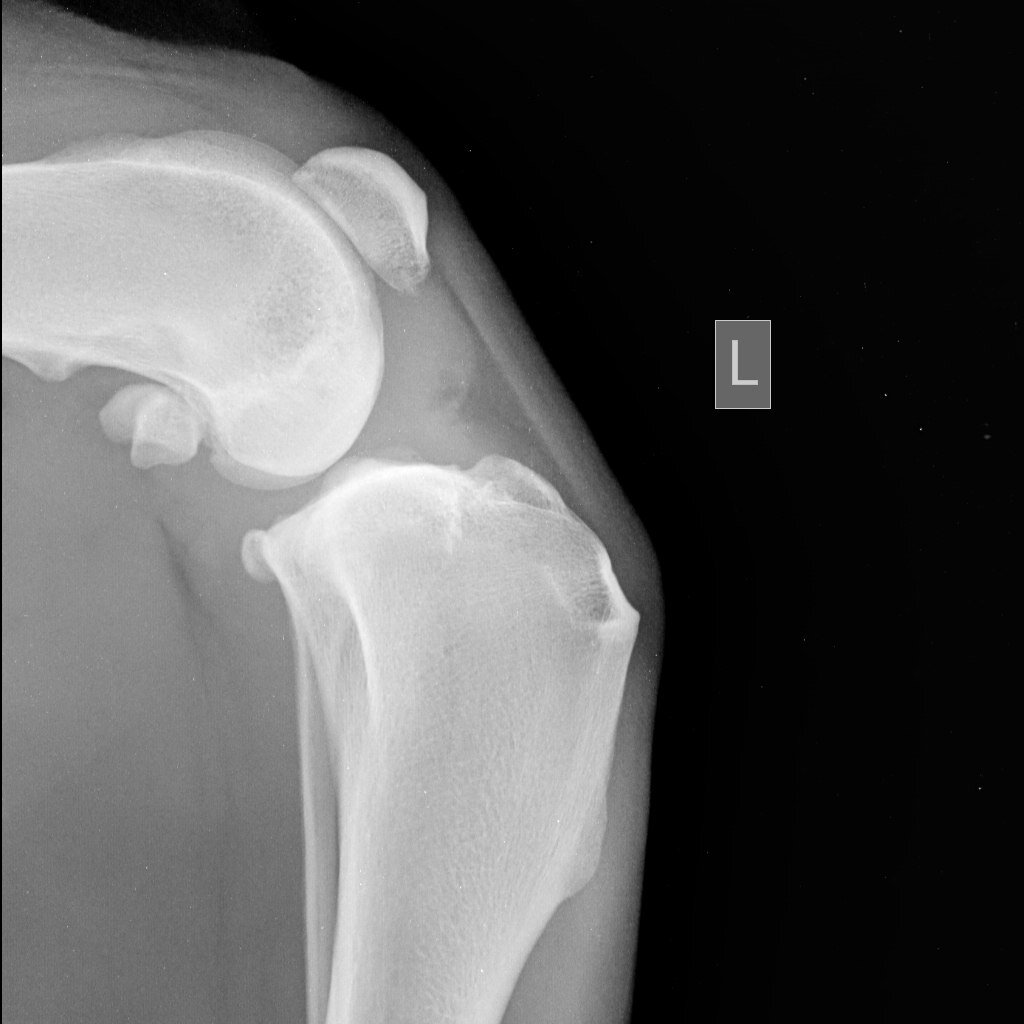

2. Диагностические мероприятия. При травмах и ортопедических болезнях поставить диагноз возможно только с помощью дополнительных обследований. Рентген, МРТ и артроскопия назначается врачом для постановки верного диагноза. При необходимости назначается забор и исследование синовиальной жидкости.